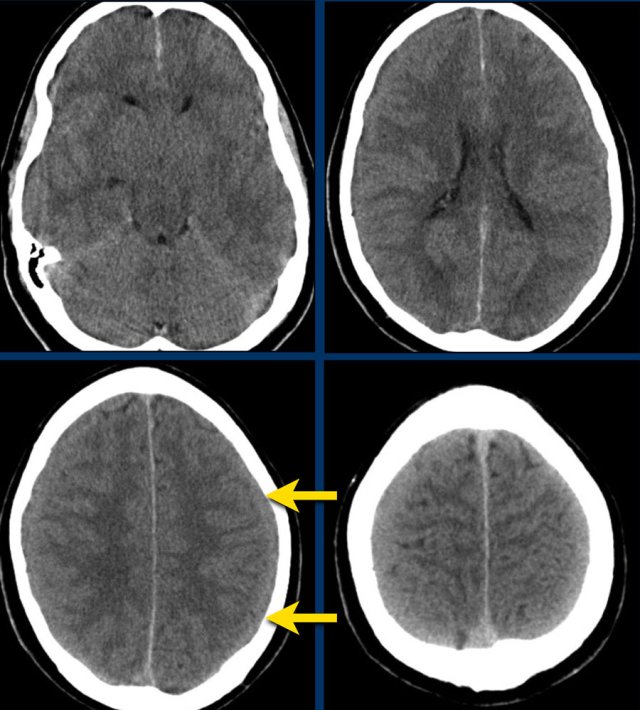

This patient has an acute subdural hematoma.

There is midline shift (left image).

The patient was operated and the hematoma was evacuated (right image).

The images show a subdural hematoma.

Notice that the hematoma has both hyperdense and isodense  areas.

This can be seen in hyperacute bleeding, but can also be seen in rebleeding.

There is displacement of midline structures with obstruction of CSF flow resulting in dilatation of the temporal horn of the right lateral ventricle (arrow).

An acute subdural hematoma is hyperdens (clotted blood), a subacute hematoma is isodens and a chronic subdural hematoma appears hypodens to brain parenchyma (isodens to CSF).